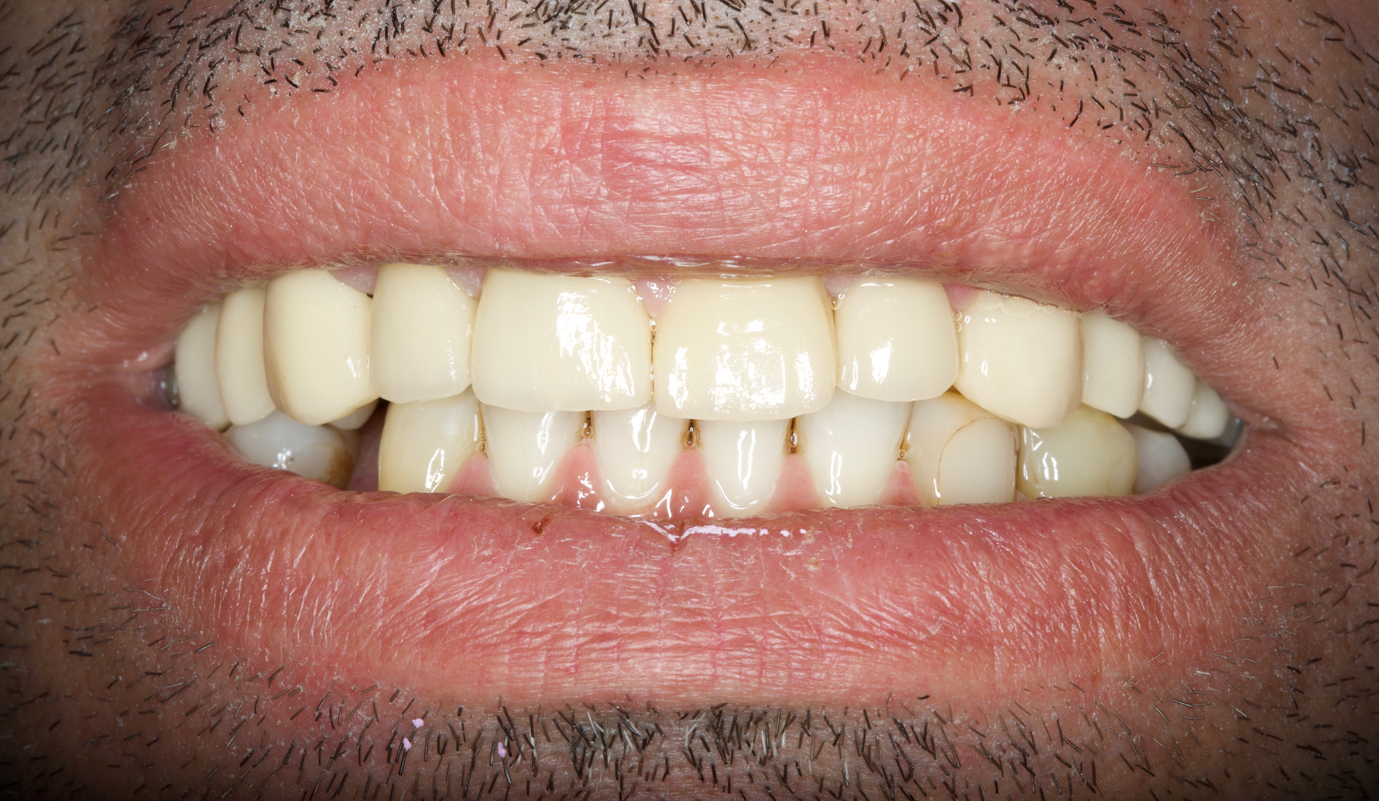

Sobre implantes as soluções podem ser para casos unitários ou múltiplos, com estruturas fixas para reabilitar arcadas totais. Estes funcionam como se fossem umas “raízes dentárias artificiais” onde são fixas as coroas cerâmicas. São soluções apetecíveis pelo facto de dar a sensação de ter novamente dentes, mas têm de ser mantidas com cuidado redobrado pois acabam por ser peças artificiais e o que pretendemos é que sejam definitivos sem que haja qualquer tipo de problema posterior.

Casos de próteses sobre implantes